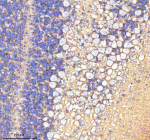

Immunohistochemical staining of ATP1A2 using anti-ATP1A2 antibody. ATP1A2 was detected in a paraffin-embedded section of human breast cancer tissue. Heat mediated antigen retrieval was performed in EDTA buffer (pH 8.0, epitope retrieval solution). The tissue section was blocked with 10% goat serum. The tissue section was then incubated with 2 ug/ml rabbit anti-ATP1A2 antibody overnight at 4oC. Peroxidase Conjugated Goat Anti-rabbit IgG was used as secondary antibody and incubated for 30 minutes at 37oC. The tissue section was developed using an HRP secondary and DAB substrate.